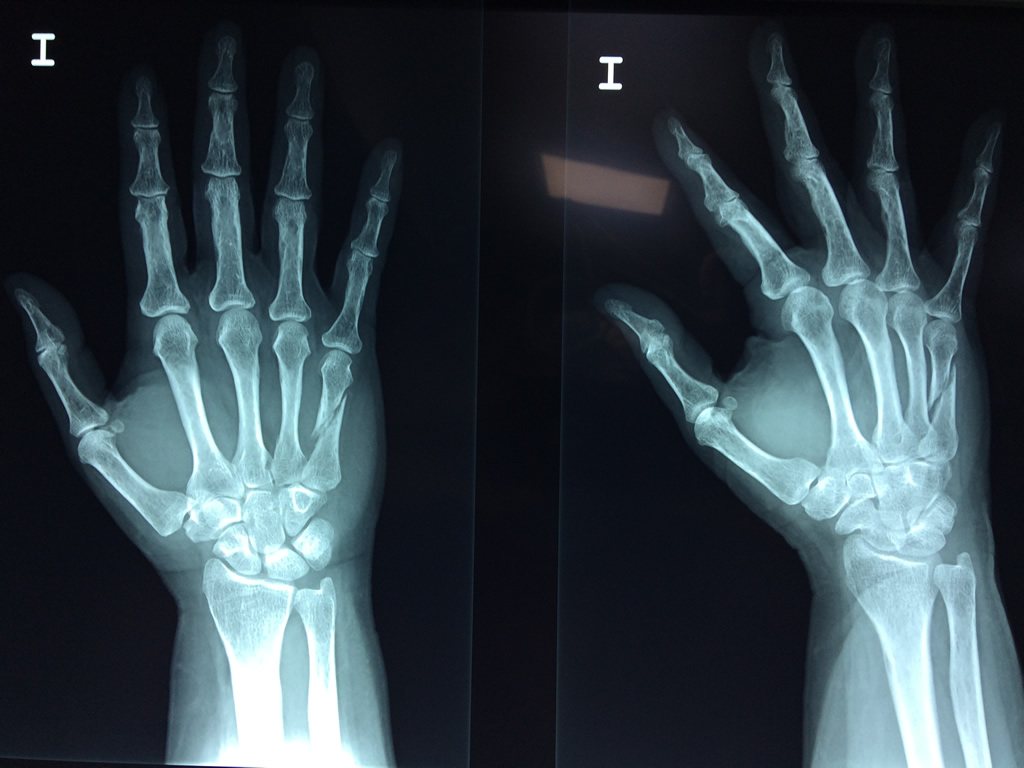

Cirugías de Codo - Cirugías de Muñecas y Manos

Los procedimientos más comunes en cirugía de la mano son aquellos destinados a reparar traumatismos, incluyendo lesiones de tendones, nervios, vasos sanguíneos, y articulaciones; huesos fracturados; y quemaduras, cortes, y otros daños de la piel.